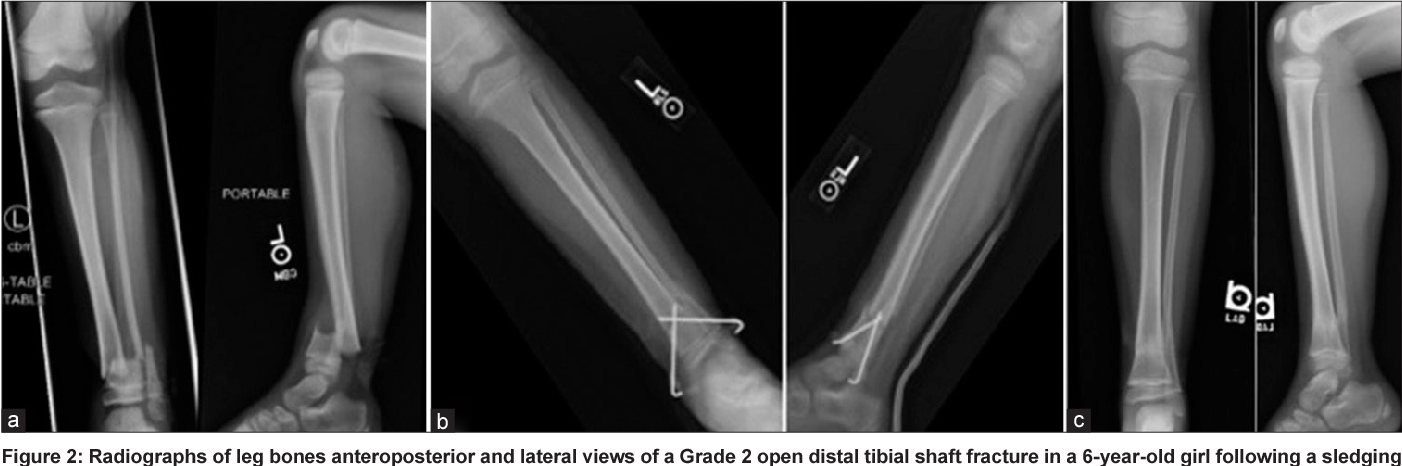

كسور القصبة والشظية عند الأطفال: أنواعها وأسبابها وعلاجها

القصبة والشظية هما العظمان الرئيسيان في الساق، حيث تقع القصبة في الجزء الأمامي والشظية في الجزء الخلفي. كسور القصبة والشظية عند الأطفال هي من أكثر أنواع كسور العظام شيوعًا في هذه المرحلة العمرية،…